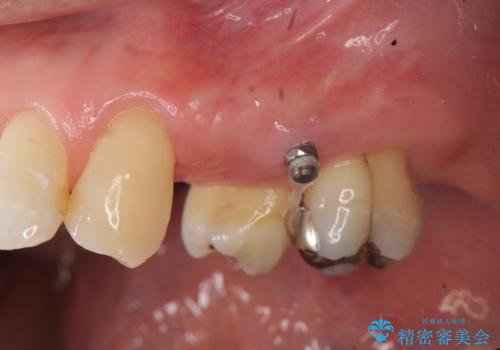

ブリッジの長期的な予後のためには支台となる歯の位置・清掃性が重要となりますが、今回ブリッジを製作するにあたり位置の悪い左上小臼歯を補綴前小矯正を行い位置を改善します。

補綴前小矯正について

矯正を行うことで歯を適切な位置に動かすことでより、清掃性に優れ長期的な予後を見込むことのできるブリッジを製作することができました。